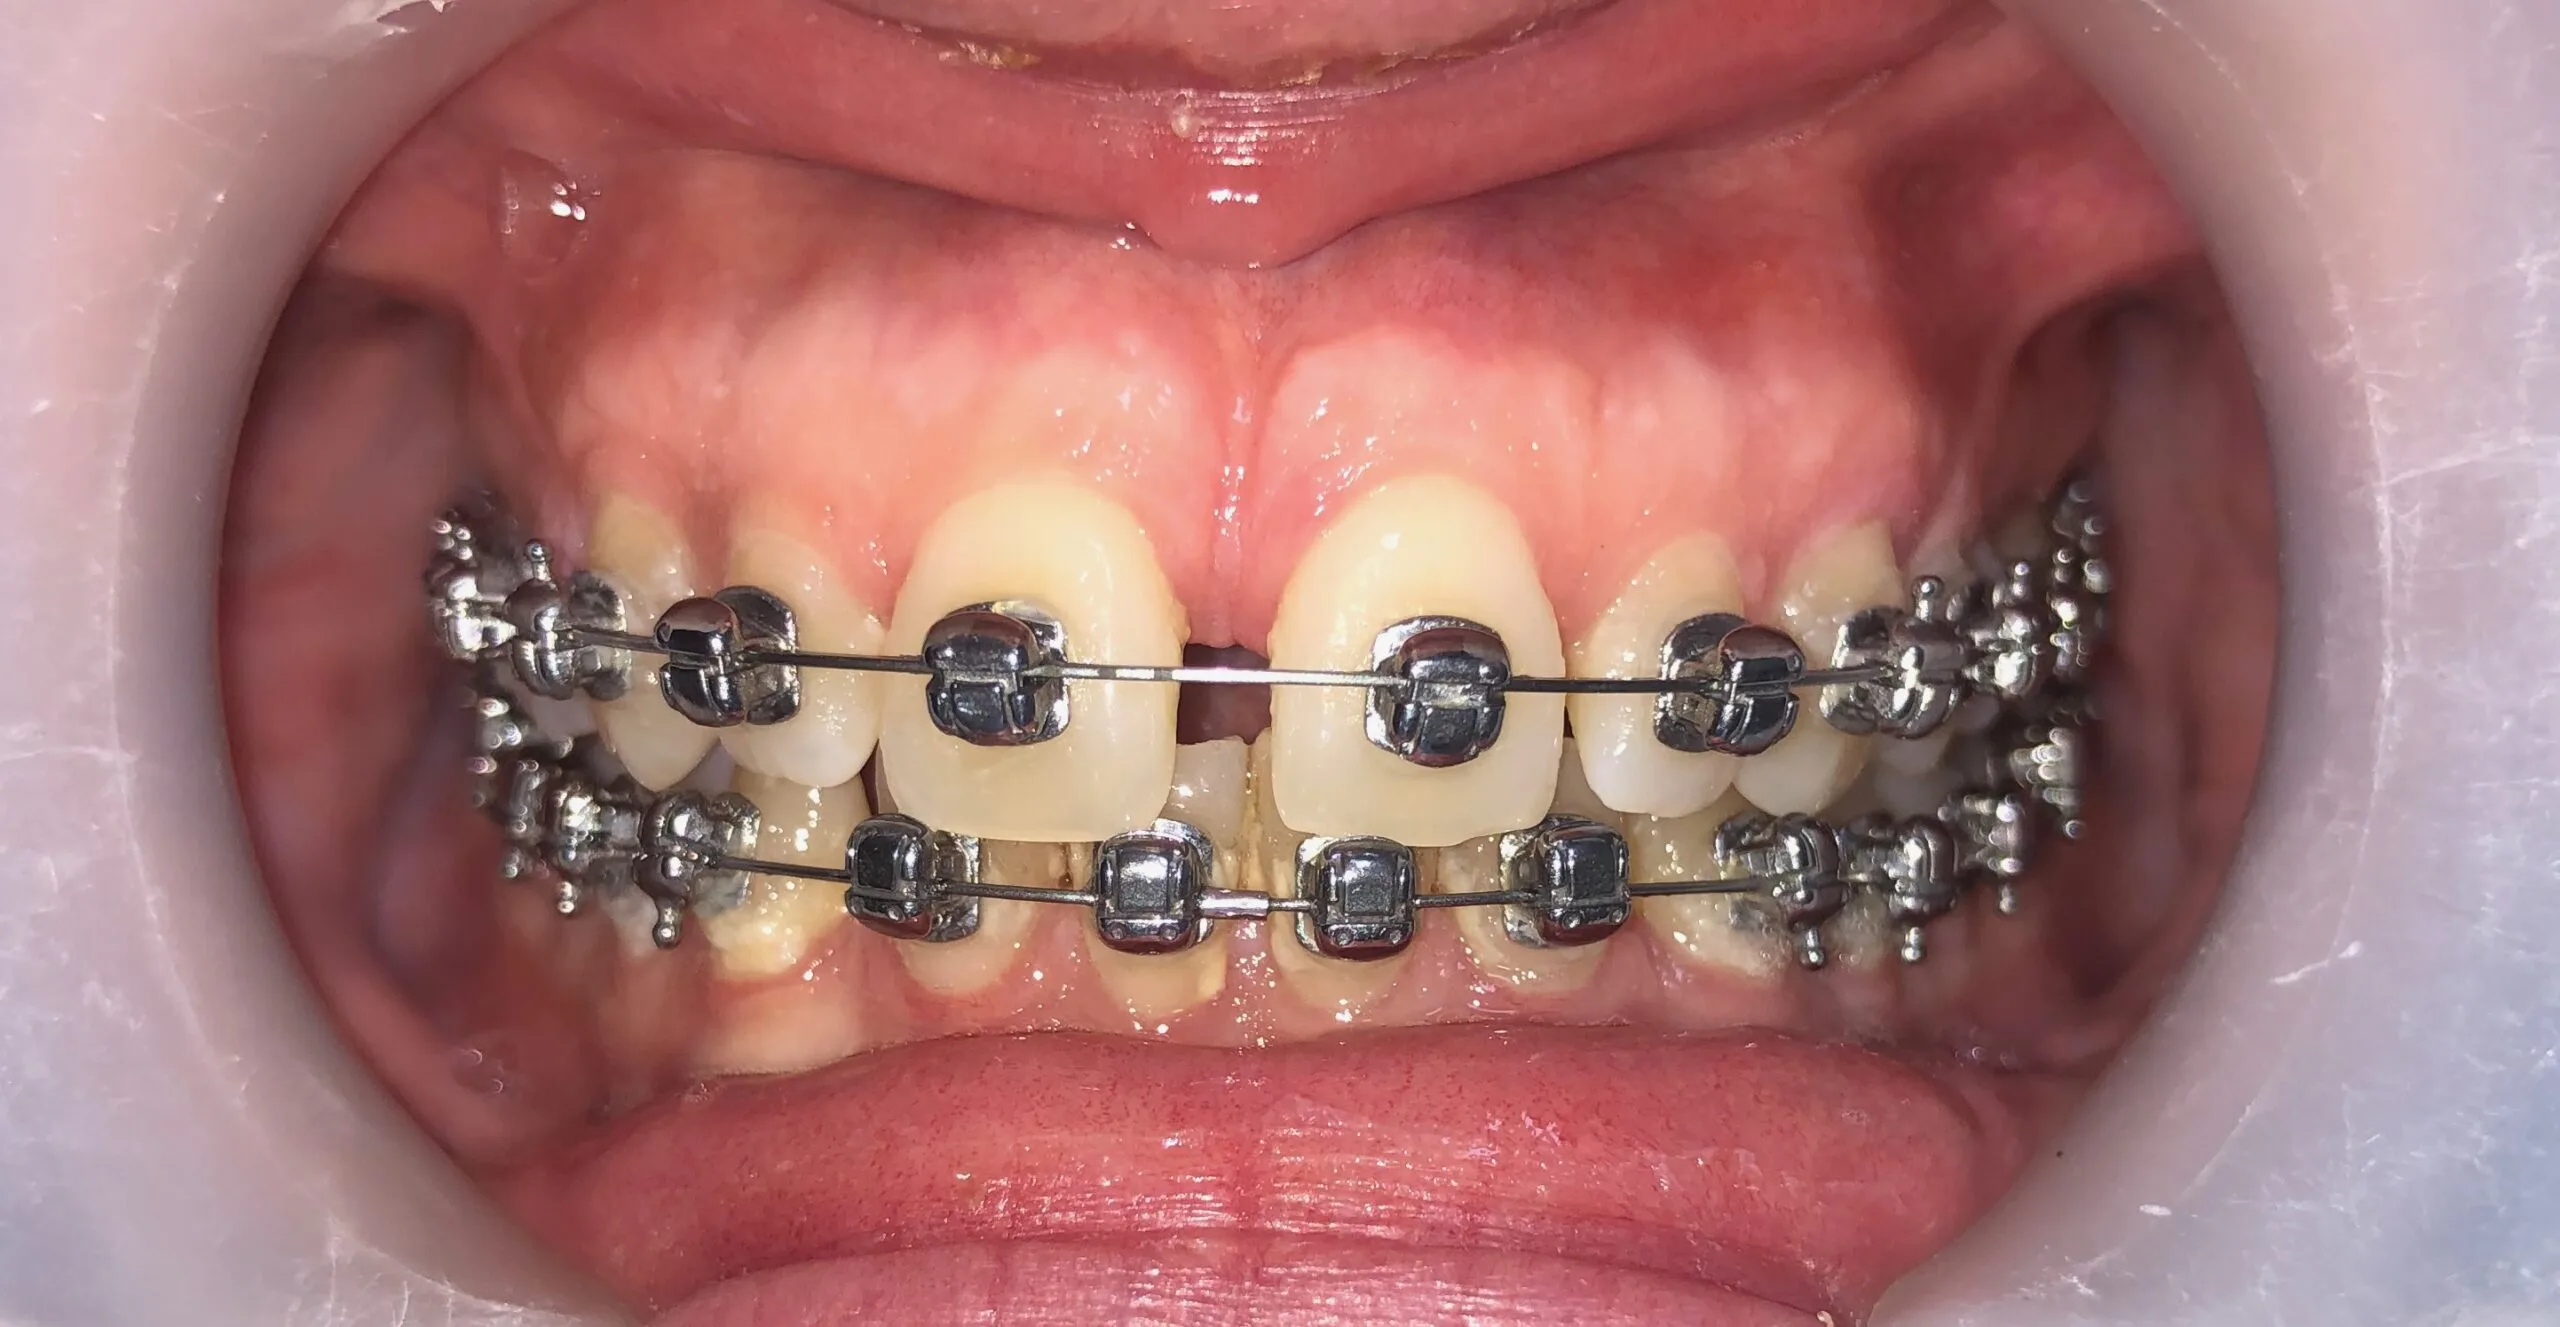

Facetas, Coroas sobre dentes e Coroas sobre implantes

Facetas cerâmicas

Coroas sobre dentes e coroas sobre implantes

Facetas, Coroas sobre dentes